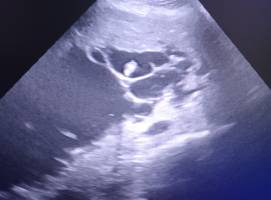

Kardiologia weterynaryjna to specjalistyczna dziedzina zajmująca się diagnostyką i leczeniem chorób serca.